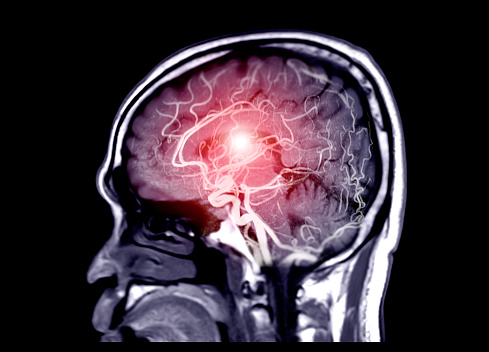

뇌질환은 한번 손상을 입으면 회복이 어렵기 때문에 매우 무섭다고 알려져 있습니다. 따라서 정확한 질환을 알고 미리 건강을 관리하는 것이 중요합니다. 그 중에서 뇌졸중 뇌출혈 뇌경색은 모두 뇌에서 발생하는 질환입니다. 오늘은 이들의 차이점을 알기 쉽게 설명해드립니다.

∎ 뇌졸중이란

뇌의 일부분에 혈액이 제대로 전달되지 않아

손상이 되는 것을 말합니다.

이는 혈관이 막히거나 터짐으로써

그 부분의 뇌가 손상되는 것인데,

다른 말로는 뇌혈관 질환 혹은 중풍이라고 합니다.